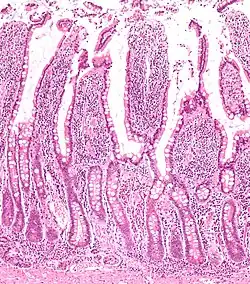

Tracing has revealed that LGR5 is a marker of adult intestinal stem cells. The high turnover rate of the intestinal lining is due to a dedicated population of stem cells found at the base of the intestinal crypt. In the small intestines, these LGR5+ve crypt base columnar cells (CBC cells) have broad basal surfaces and very little cytoplasm and organelles and are located interspersed among the terminally differentiated Paneth cells.[12] These CBC cells generate the plethora of functional cells in the intestinal tissue: Paneth cells, enteroendocrine cells, goblet cells, tuft cells, columnar cells and the M cells over an adult's entire lifetime. Similarly, LGR5 expression in the colon resembles faithfully that of the small intestine.[12]